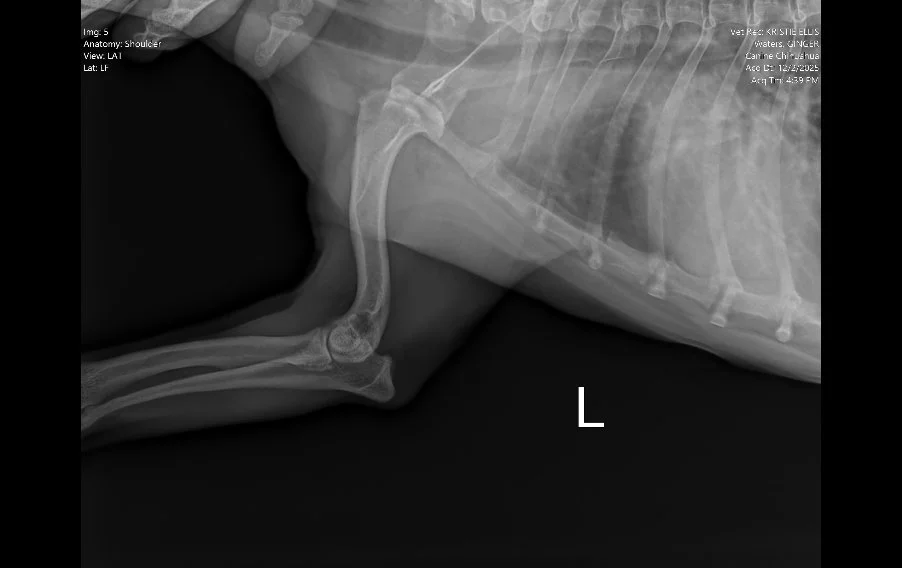

Image 4. Lateral radiograph of the left shoulder.

Radiographs (Images 1–4) of the left forelimb, including the carpus, elbow, and shoulder identified:

• Mild degenerative joint disease (arthritis)

• Decreased shoulder joint space

• No fractures, masses, or bone lysis

Based on these findings, Ginger was treated for osteoarthritis. However, her clinical progression did not match the imaging results.